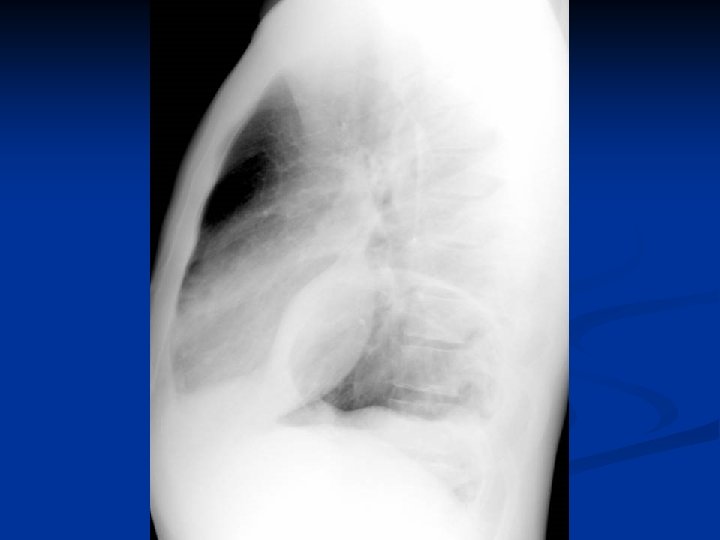

Metode de diagnosticare